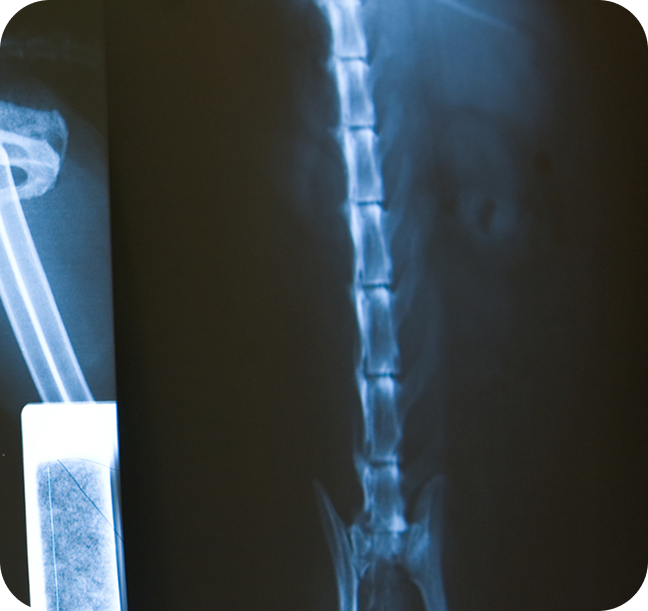

At Animal Ark Animal Hospital, we offer a full range of diagnostic services for dogs, cats, and exotic small mammals, all conveniently available under one roof. Whether your pet requires routine lab work or advanced imaging, we provide digital X-rays to assess bones, joints, and internal organs, ultrasound imaging for detailed soft tissue evaluations, and in-house laboratory testing to deliver fast results in urgent situations. To ensure the most accurate diagnoses and highest standard of care, we also collaborate with board-certified veterinary radiologists. Our trusted partners include Dr. Erica Baravik-Munsell, DVM, DACVR of Infinity Veterinary Imaging, who performs ultrasounds, and Dr. Rachel S. Moon, DVM, DACVR, who provides expert interpretation of radiographic studies. Together, our in-house capabilities and specialist consultations allow us to identify and address a wide range of conditions—from orthopedic issues to complex internal health concerns—with precision, speed, and compassion.

Non-Invasive X-ray & Ultrasound Imaging

Our state-of-the-art diagnostic tools include: